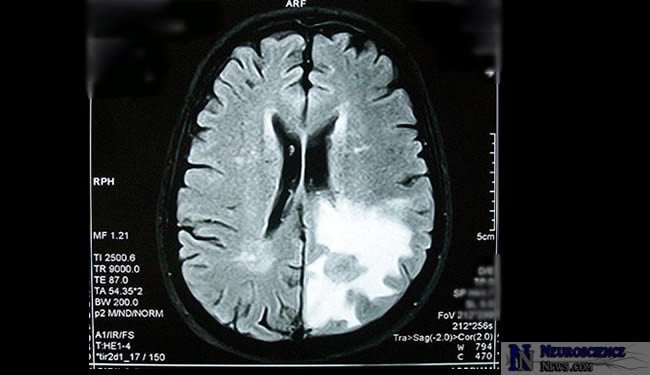

Breast Cancer Patients’ Brain Tissue Altered by Chemotherapy

Brain imaging studies of women with breast cancer before and after chemotherapy treatments show grey matter is being affected during the chemotherapy treatments. Brain areas believed to be critical for multi-tasking, memory and other cognitive functions were seen to change during the chemotherapy.